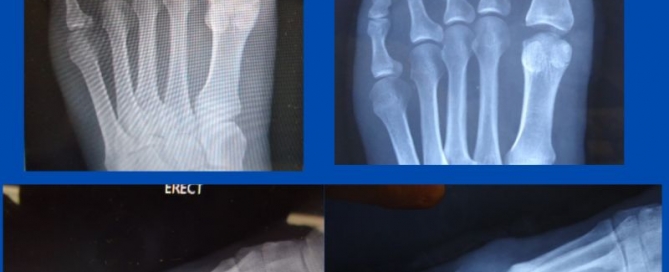

Dislocated 2nd MTPJ

Blog's main page This patient presented recently with a long-standing markedly painful left 2nd metatarsophalangeal joint (MTPJ). Conservative care has been unsuccessful and hence she was referred for a surgical [...]